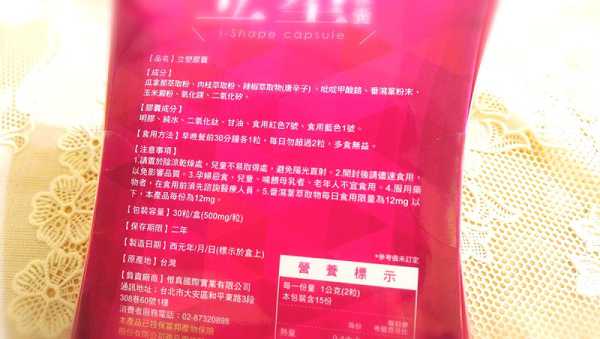

Supercut塑魔纖立塑膠囊的成分有:瓜拿那萃取粉、肉桂萃取粉、辣椒萃取物(唐辛子)、吡啶甲酸鉻、番瀉葉粉末、玉米澱粉、氧化鎂、二氧化矽。

之前上過相關課程,成分表是依照每項成分的多寡來排列順序,排在最前面的就是產品的主要成分!

食用方式:早晚餐前30分鐘各1粒,每日不超過2粒。(多食無益)

番瀉葉萃取物每日食用限量為12mg以下,

番瀉葉萃取物每日食用限量為12mg以下,